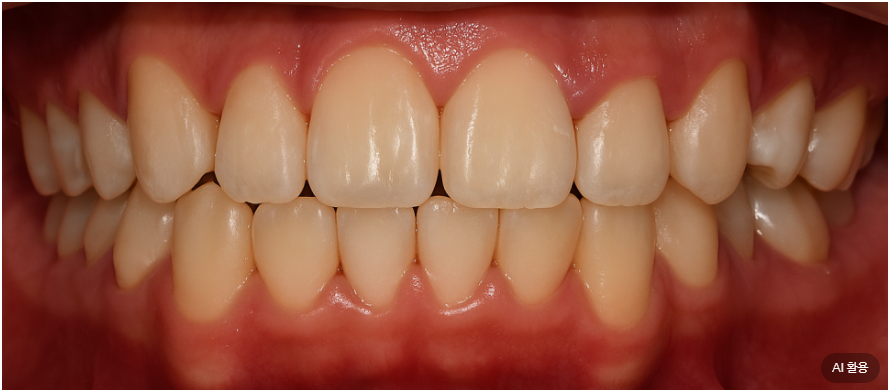

| 3. 종결 단계

25.06.12

매복되었던 치아는

완전히 정상 위치로 나와서

제 기능을 다하게 되었고,

사랑니도 성공적으로

어금니 자리에 정착하여

저작 기능을 담당하게 되었습니다.

특히 주변 치조골도 자연스럽게 재생되어

마치 원래부터 그 자리에 있었던 것처럼

건강한 상태를 보인다는 거예요.

절단연 교합은 완전히 개선되어

윗니가 아랫니를 적절히 덮는

정상적인 교합 관계가 확립되었고,

정중선도 완벽하게 일치하여

기능적으로나 심미적으로나

만족스러운 결과를 얻었습니다.